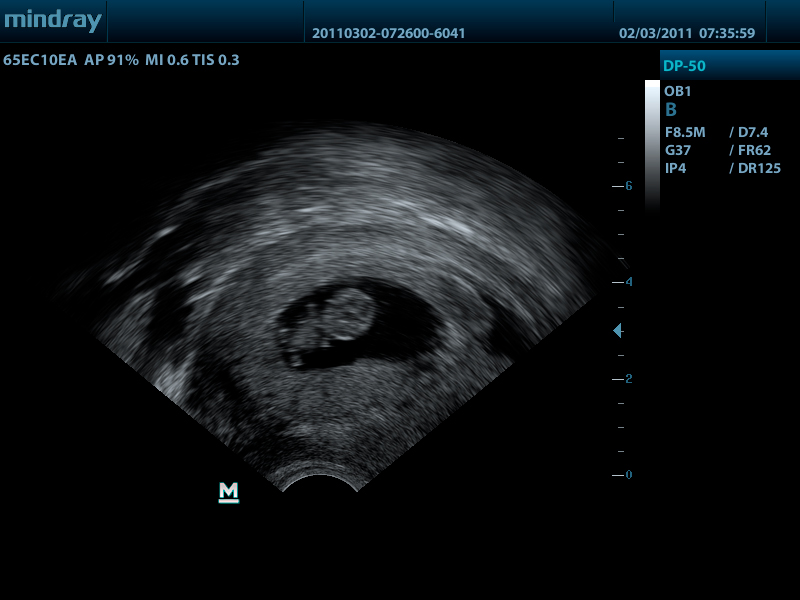

Mindray DP-50 – портативная цифровая ультразвуковая система с ЖК монитором 15 дюймов (1024Х768)

и встроенными аккумуляторными батареями (опция) позволяющими работать в автономном режиме до 2-х часов.

DP-50 – портативный УЗИ сканер разработан на базе новой платформы X-treme engine, используемой в хорошо зарекомендовавших себя цветных сканерах с доплером моделей DC-3, DC-7, DC-6. Эта платформа открывает возможности для расширений до уровня цветных сканеров и совместимости с широким диапазоном периферийного оборудования. X-treme означает интеллект, высокую скорость обработки данных, многоуровневую передачу сигналов, а также возможность оптимизации изображения и модульного расширения.

Применяемые датчики DP-50:

Внутриполостной датчик 65EC10EA (5.0/6.5/7.5/8.5/Н8.0/Н9.0 МГц, R-10 )